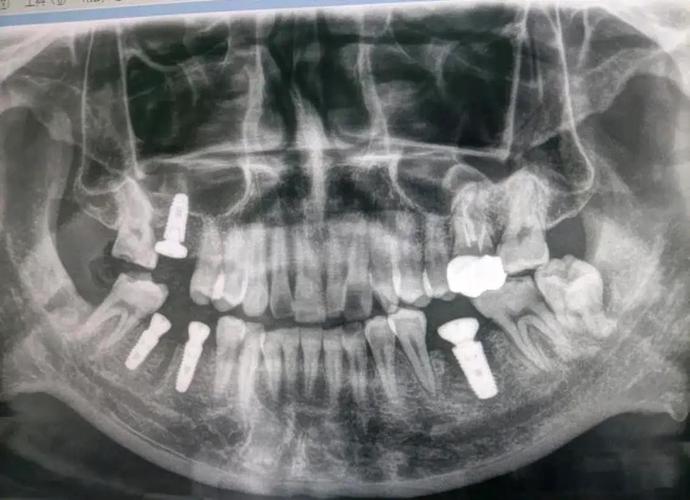

- 图像重建:扫描结束后,计算机自动将二维数据重建为三维图像(包括冠状面、矢状面、横断面及三维重建模型),医生可多角度观察。

结果解读与方案设计

CT报告通常包含以下内容,医生会结合报告制定个性化种植方案:

- 骨量评估:牙槽骨高度、宽度、厚度数据,是否达到种植标准(如下颌后牙区骨高度需≥12mm,避开下颌神经管;上颌后牙区骨高度需≥15mm,避免穿透上颌窦底)。

- 解剖结构位置:下颌神经管距离牙槽嵴顶的距离(理想≥2mm)、上颌窦底厚度(若<1mm需行上颌窦提升术)、颏孔位置(避免损伤颏神经)。

- 骨密度分级:根据CT灰度值分为D1-D4型,D1型(致密骨)需高扭矩植入,D4型(疏松骨)可能需植骨或选择表面粗糙的种植体以增强初期稳定性。

- 种植方案设计:包括种植体品牌、型号(长度、直径)、植入角度(通常与牙长轴呈15°-30°以避开邻牙牙根)、是否需植骨或使用种植导板(3D打印导板可提高植入精度0.5-1mm)。